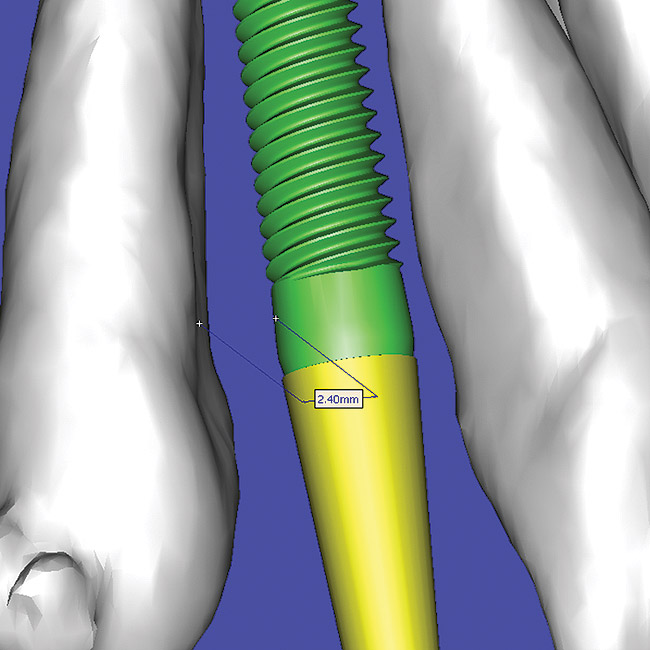

Using the interactive treatment-planning software application, the scan data was assimilated and both potential lateral incisor implant receptor sites were evaluated. It is a combination of the data and the methodology used to interpret the data that is the basis for defining a new paradigm in diagnosis and treatment planning. Proper evaluation of these images and correct use of the interactive treatment planning software tools is essential in creating a decision tree of treatment options. First, the data from the scan was reformatted into panoramic, axial, and cross-sectional images. The undistorted cross-sectional images revealed the residual alveolar bone in the area of the right lateral incisor. Then, a simulated schematic implant was placed within the bone with an abutment extension to help visualize the connection to the restorative position of the tooth (Figure 6). The Triangle of Bone® (TOB), a concept developed by the author to analyze bone quality, quantity, and disposition at prospective dental implant sites using CBCT scans, aided in determining available bone volume by defining a “zone” for proper implant placement18,19 (Figure 7).

After reviewing the CT data and the decision tree, the bone within the “zone” of the TOB was evaluated and found to be satisfactory for implant placement. Because the goal of implant dentistry is not the implant but the tooth that is placed, true restorative-driven implant dentistry must begin with the assumption that the implant position should remain consistent with the tooth it is replacing, and the final implant-supported restoration.12,22-26 The TOB aids the clinician in understanding the link between the implant position and the desired restorative goal. The base of the geometric shaped “zone” is visualized by starting at the widest area of alveolar bone facially and superiorly. The apex of the triangle is positioned to bisect the alveolar crest (Figure 7). The TOB, the overlay in the cross-sectional image, reveals whether adequate bone is available for implant placement. It also helps to identify concave facial bone defects, and accurately determine the width of bone at the crest. The author recommends using an interactive software application that provides the necessary measurement tools to accurately assess the bone anatomy.

Figure 7  SOFTWARE IMAGING The determination of the

Figure 7